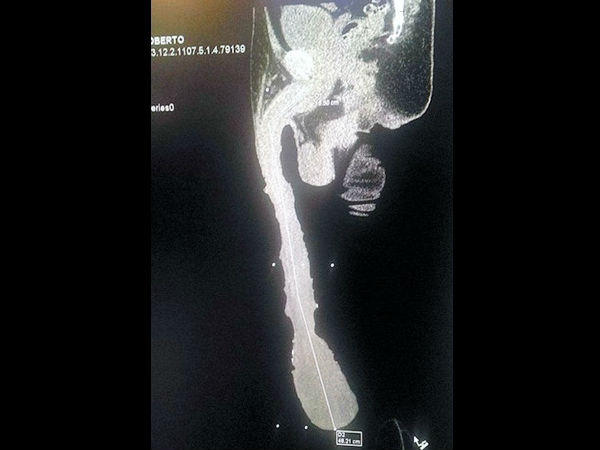

18.9 இன்ச் ஆணுறுப்புடன் வாழ்ந்து வரும் அதிசய மனிதன்; ஊனமுற்றவர் என அறிவிக்க கோரிக்கை!!!

ராபர்டோ எஸ்க்யூவெல் கேப்ரேரா

மெக்ஸிகோவை சேர்ந்த 52 வயதானவர், ராபர்டோ எஸ்க்யூவெல் கேப்ரேரா. இவரது ஆணுறுப்பு தான் 18.9 இன்ச் உள்ளது. இதனால் மற்றவர் பெருமையாக கருதினாலும், நான் மிகவும் வெறுப்பாக தான் இருக்கிறேன் என கூறுகிறார் ராபர்டோ எஸ்க்யூவெல் கேப்ரேரா.

மருத்துவர் கொடுத்த அறிக்கையில் அதிர்ச்சி

இதற்காக மருத்துவ அறிக்கை இவர் சமர்பிக்க வேண்டி இருந்தது. அப்போது இவரை பரிசோதித்த மருத்துவர், ராபர்டோ எஸ்க்யூவெல் கேப்ரேராவின் ஆணுறுப்பு 6 இன்ச் தான் இருக்கிறது. மற்ற பகுதி வெறும் சதை தான் என மருத்துவ அறிக்கையில் தெரிவித்தார்.

அளவை குறைக்க ஏற்பாடுகள்

இதனால், இவரது ஆணுறுப்பின் அளவை குறைக்க ஏதேனும் ஏற்பாடுகள் மேற்கொள்ளலாம் என மருத்துவர்கள் ஆலோசித்து வருகிறார்கள்.